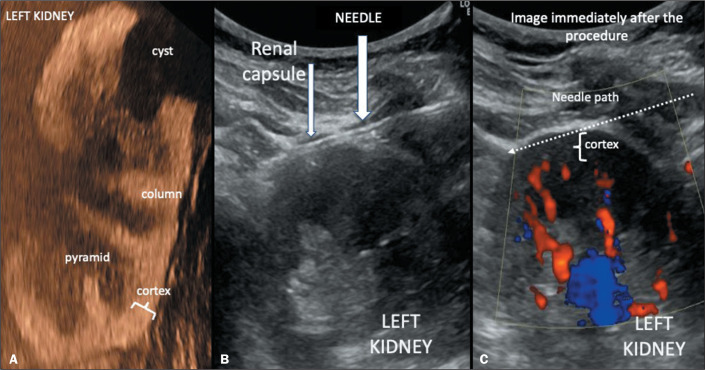

Materials and methods: This retrospective observational study examined the pathology results and evolution of 244 patients referred for ultrasound-guided renal biopsy at a single center. In each biopsy, the needle was advanced in the cortex just below the renal capsule. The pathologist examined the fragments, counting the viable glomeruli obtained; additional punctures were performed if necessary, as long as Doppler ultrasound showed no bleeding. The patients remained at rest at the clinic, being discharged after a follow-up ultrasound evaluation and contacted one week later to investigate late adverse events.